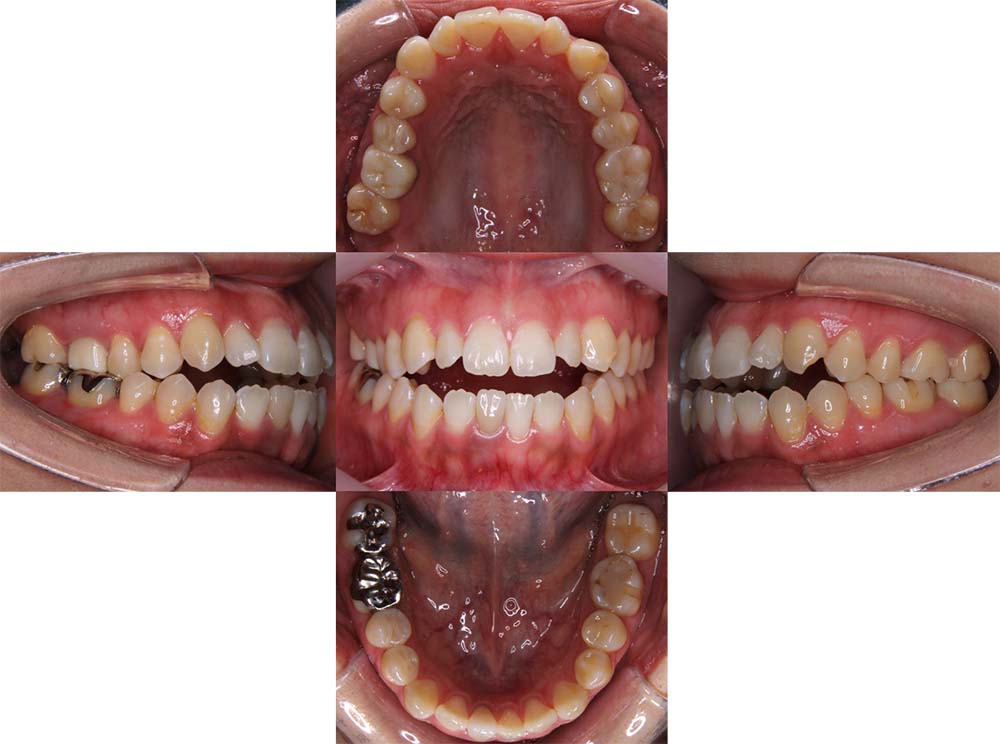

症例04

| 主訴 | 歯並びのガタガタと出っ歯が気になる。 |

| 診断名あるいは主な症状 | 上顎前突、叢生 |

| 年齢/性別 | 16歳・女性 |

| 矯正ステージ | 大人の矯正治療 |

| 治療方法 | ワイヤー矯正 |

| 抜歯部位/抜歯有無 | 抜歯 |

| 治療内容 | 抜歯したスペースを使用し、ガタガタの改善と上下顎前歯を後退させた。 |

| 費用 |

85万円程度(2025.10時点の料金となります。) ※矯正基本料金、審美ブラケットを含む |

| 治療期間 | 2年5ヶ月 |

| 主なリスク・副作用 | 痛み、歯根吸収、歯肉退縮、虫歯、後戻り |